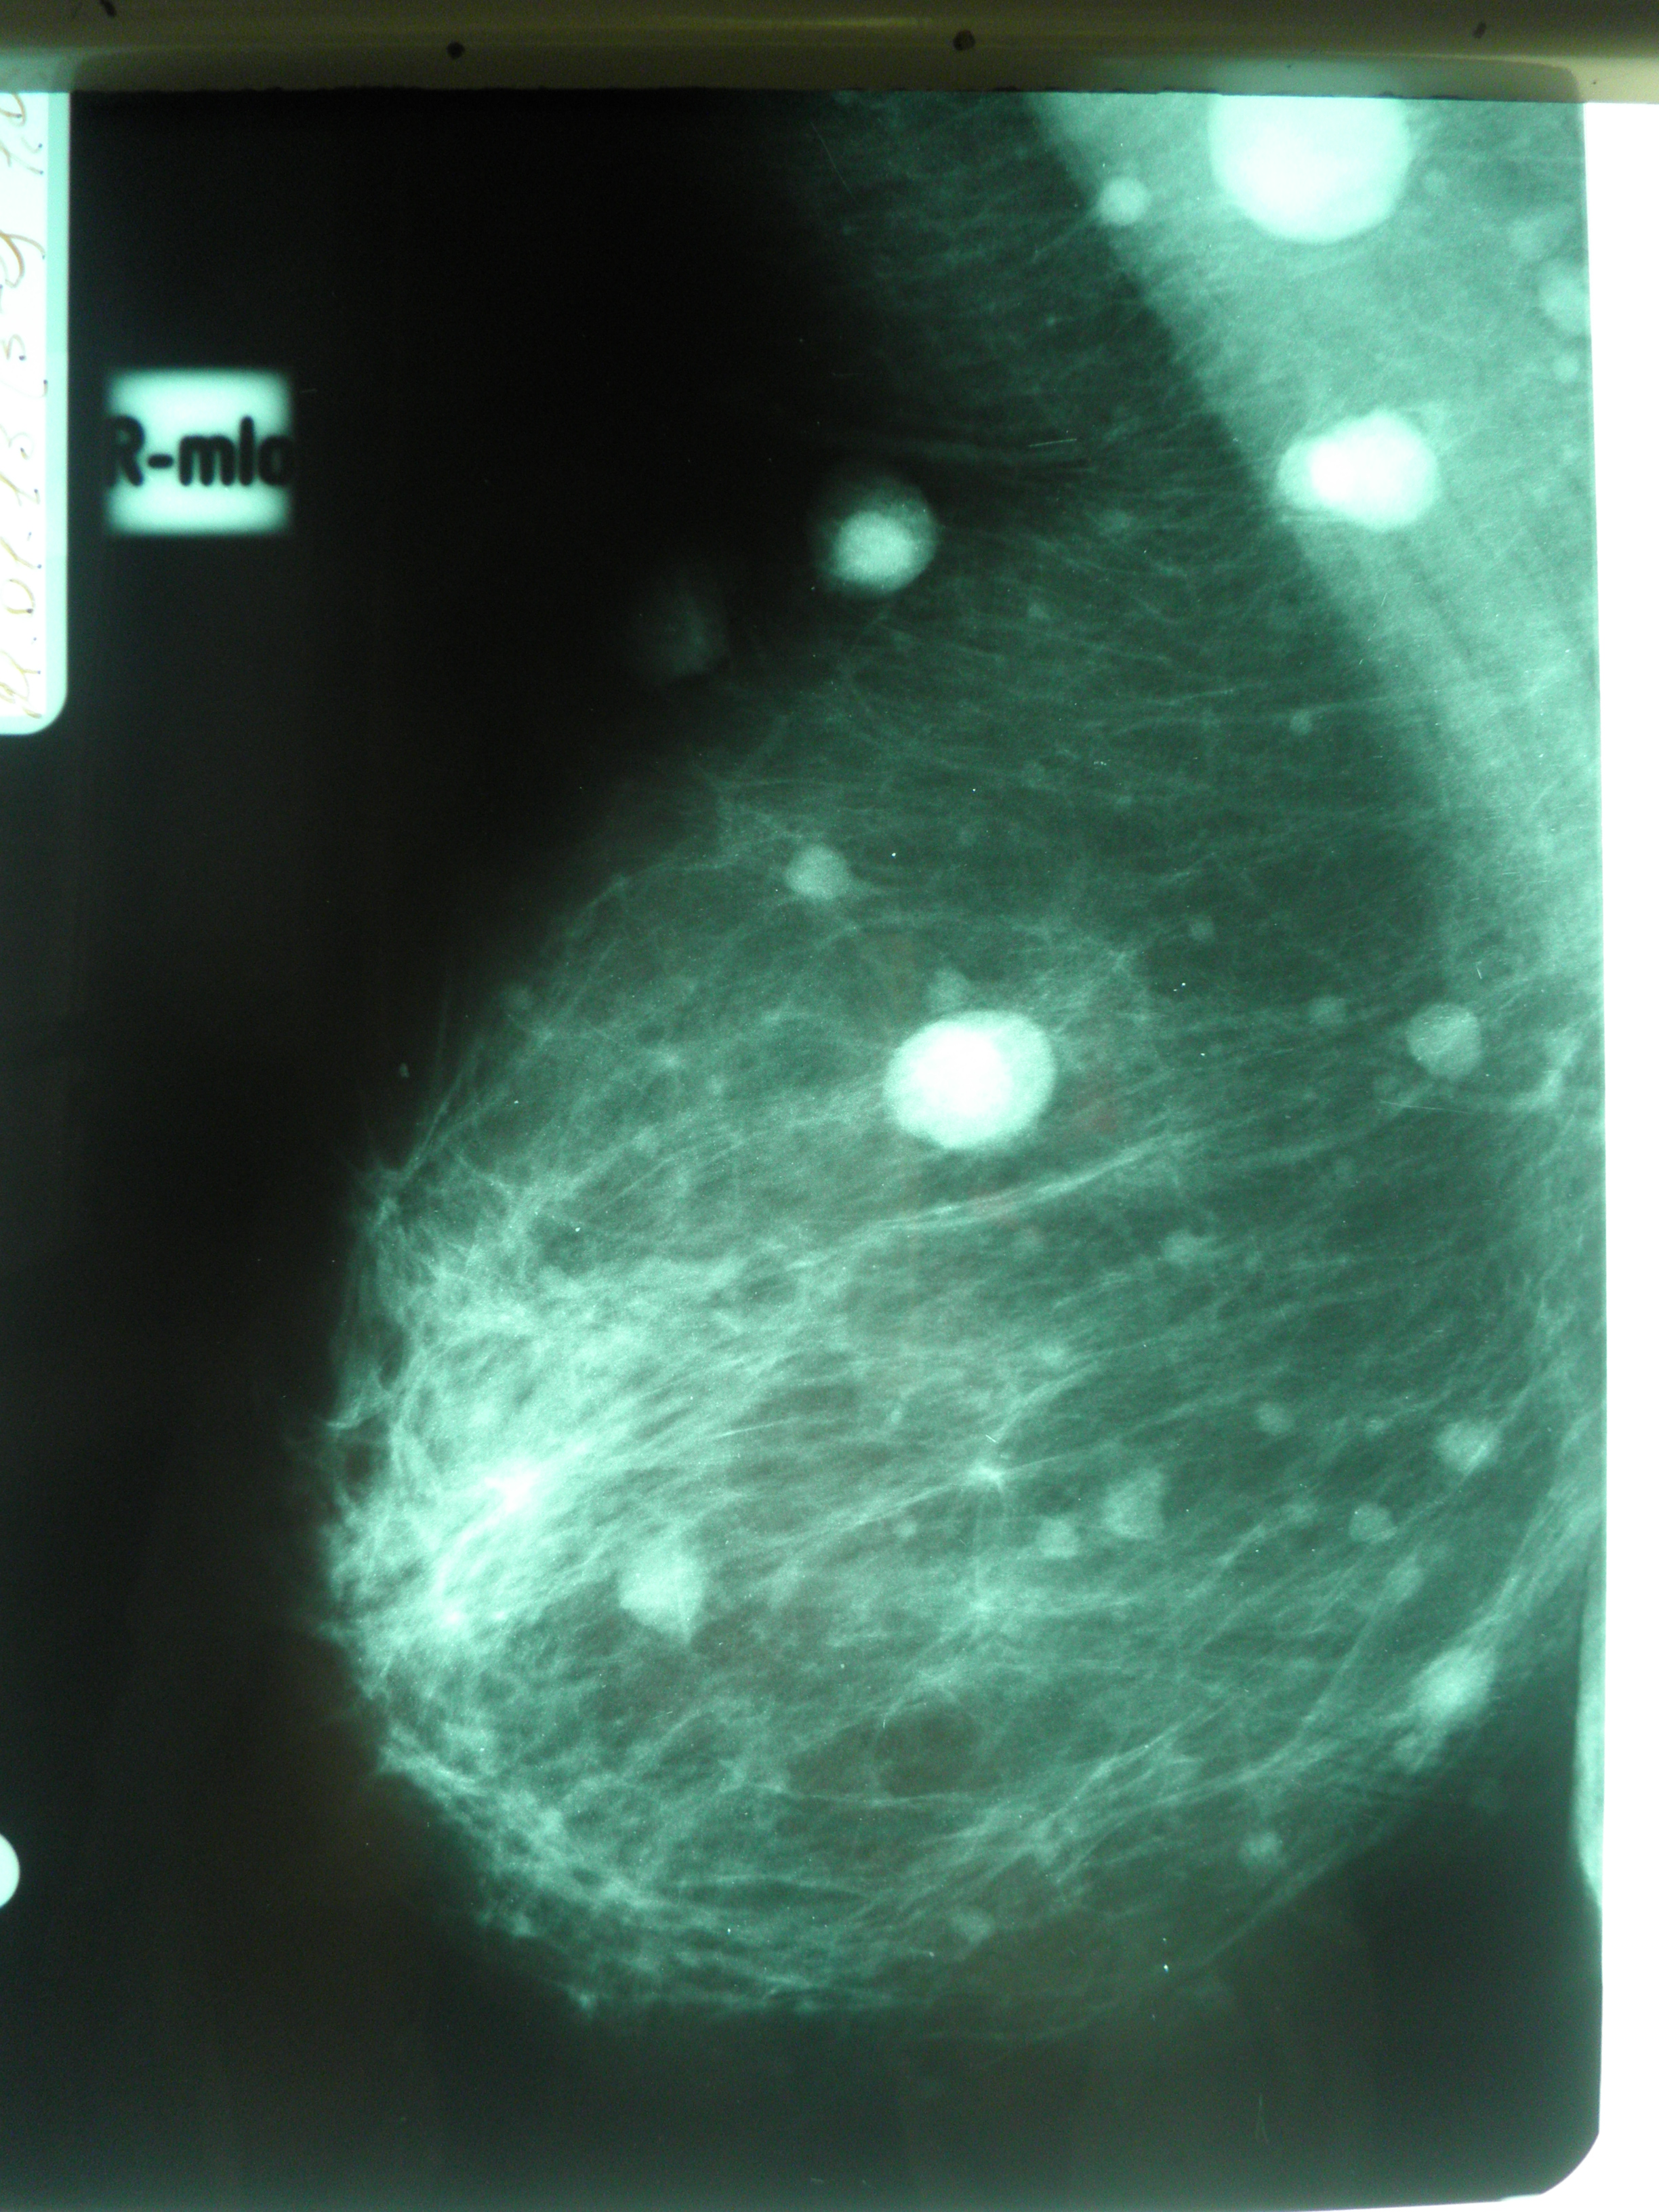

Фиброаденома молочной железы - доброкачественное образование, которое часто встречается у женщин. Оно может быть обнаружено при помощи различных методов диагностики, включая маммографию. Ниже представлены фотографии, помогающие понять, как выглядит данное заболевание.

Маммография и ее роль в диагностике фиброаденомы молочной железы

Маммография - это рентгенологическое исследование молочных желез. Оно позволяет выявить различные изменения в тканях, включая фиброаденому. На маммограммах можно увидеть структурные особенности опухоли и отследить ее динамику во времени.